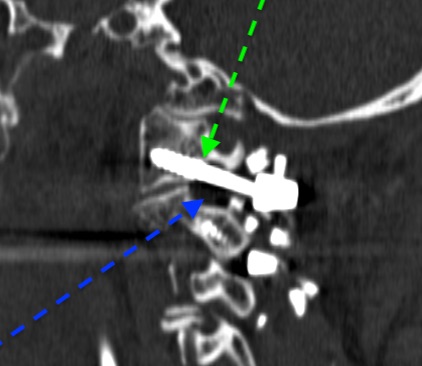

El tornillo que se fija en masa de C1 posee un segmento roscado y otro liso (flecha verde). En el foramen C1-C2 se encuentra la raíz C2 (flecha azul).

El tornillo que se ancla en la pars pasa cerca del canal de la arteria vertebral (flecha roja)